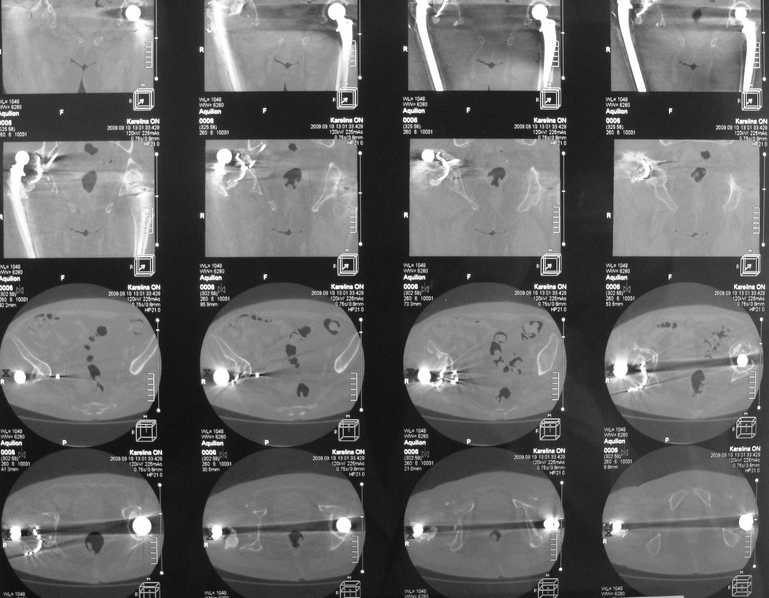

Еще КТ.